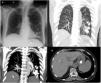

After the procedure, the patient developed low-grade fever, and a chest X-ray was requested (Fig. 1a), in which several hyperdense nodular images were observed in the middle and lower left fields and in the gastric chamber. The examination was extended with a chest computed tomography (Fig. 1b-c), which confirmed multiple high-density images in the left lung. Fig. 1d shows the hyperdense content in the stomach. A diagnosis of bronchoaspiration of embolization material was established.

(a) PA chest X-ray. Multiple high-density nodular opacities in middle and lower left fields and in the epigastrium. (b) Contrast-enhanced CT chest with MIP reconstruction. Hyperdense extravascular embolization material in the middle and lower left field. (c) Contrast-enhanced CT chest with MIP reconstruction. Bilateral hyperdense embolization material in the left lower lobe, larger than the pulmonary vessels. (D) Embolization material inside the stomach.